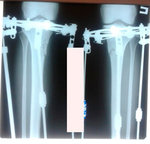

Исходник - 38 лет.

Дата операции - 07.11.2019г.

Диагноз: Варусная деформация голеней. Ротация справа.